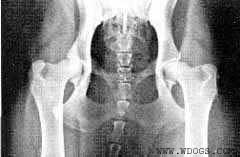

Тазобедренный сустав - подвижное

сочленение костей, образованное

суставной впадиной таза (вертлужной

впадиной) и головкой бедренной кости.

Тазобедренный сустав - простой,

трехосный, по форме шаровидный.